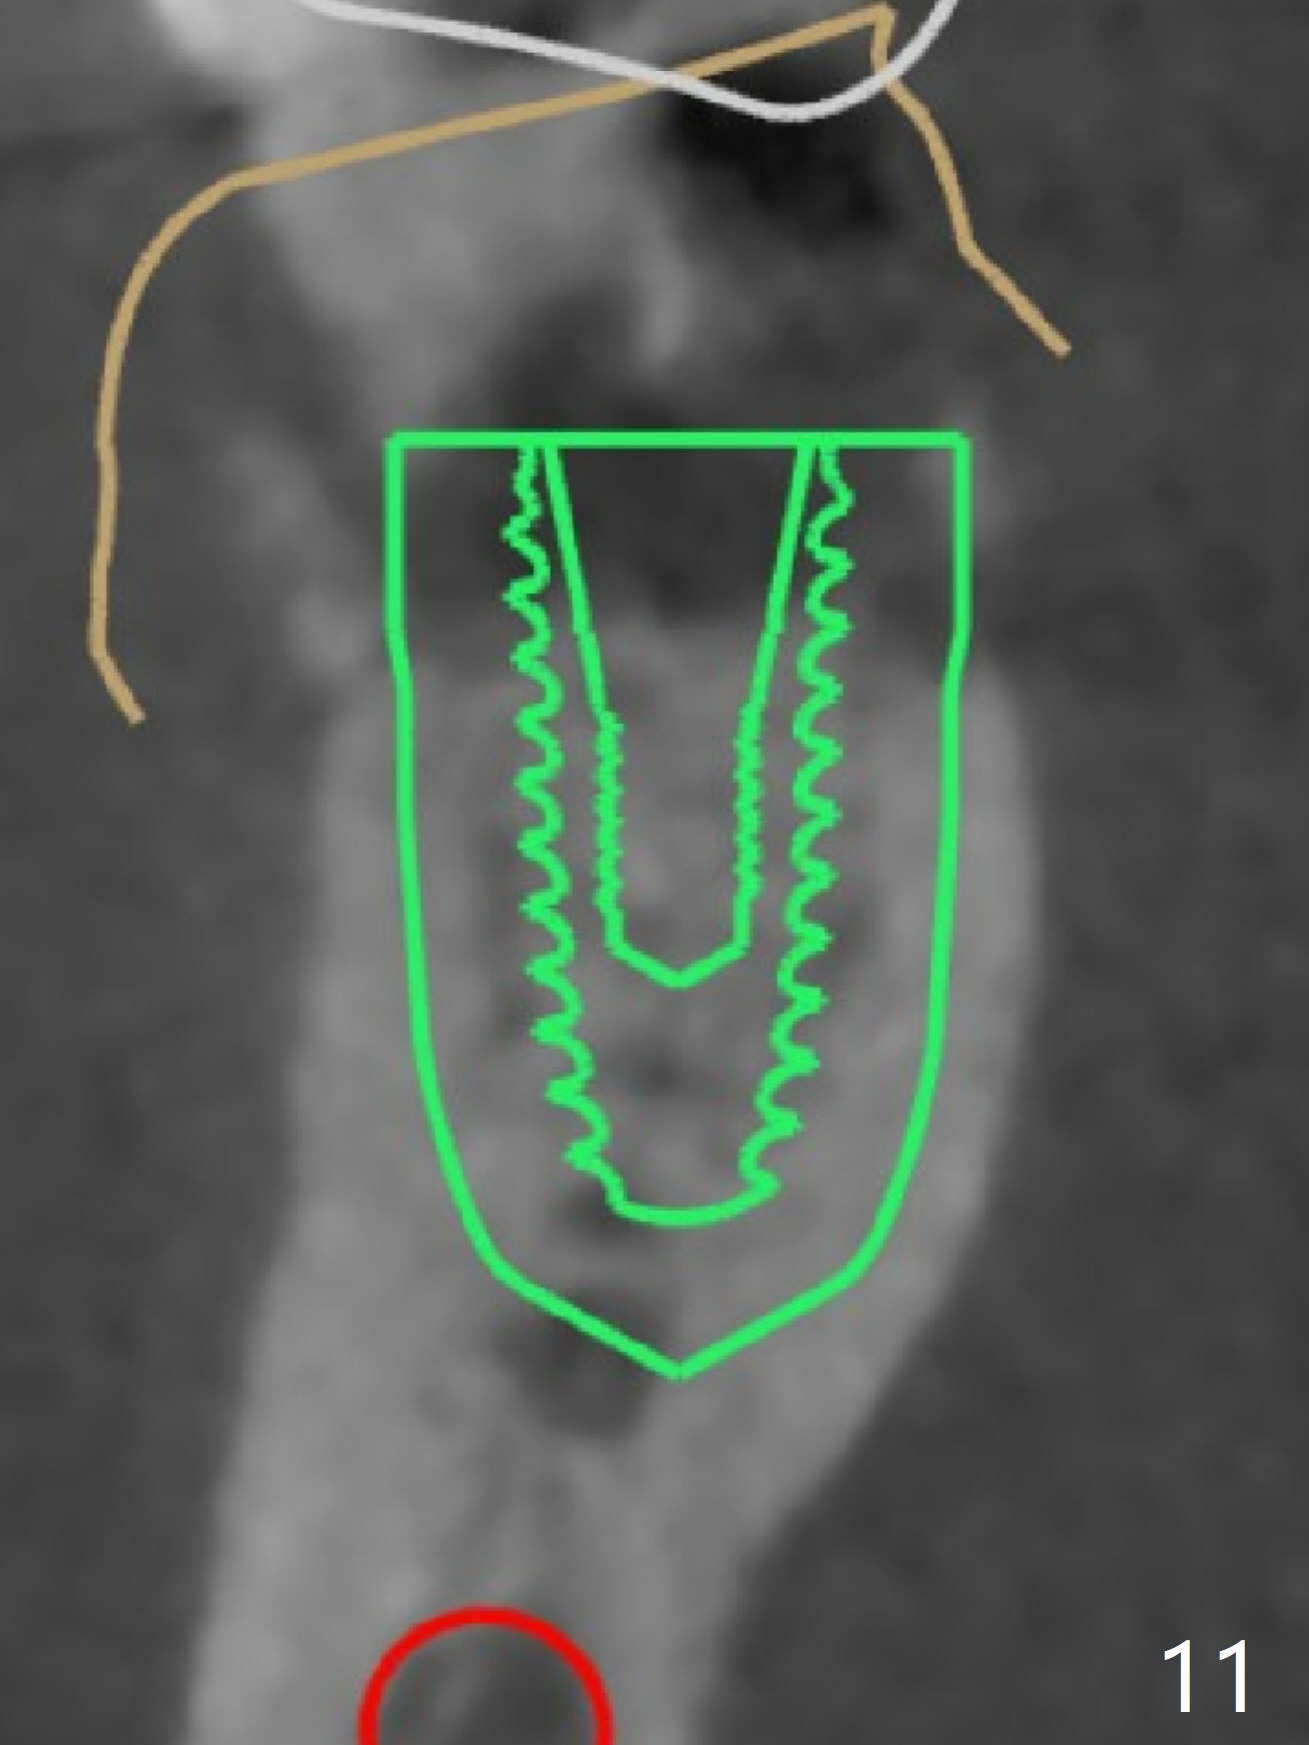

As planned, the crown of the tooth #30 with lingual (Fig.1 L) caries is removed and flattened with surgical handpiece so that the guide is able to be seated without interference. The osteotomy by 10.5 mm offset bone trimmer is lingual (Fig.2 white circle; due to in part the lingual caries and in part design error); in order to let the osteotomy to bounce back buccal, the part of the buccal roots are removed by surgical bur (arrows). The initial osteotomy by 2.2 mm drill is in the middle of the septum (Fig.3). After the last drill (3.5x11.5), the remaining roots are easily removed with proximators; a 4x11 mm dummy implant is placed with low stability and supracrestal lingual (Fig.4). Therefore a 4.5x9 mm final implant is placed with low torque. Following 4x11.5 mm drill, the torque increases to 20 Ncm. With insertion of healing screw, sticky bone (Fig.4 *: .5-1 mm cortical/cancellous allograft) is heavily packed around the implant (arrow), which apparently allows removal of the healing screw and placement of a 6x5.7(3) mm pair abutment without loosening the underlying implant. More bone graft is placed (Fig.6), followed by 2 pieces of PRF membranes. Although the implant is slightly buccally placed (Fig.7, due to over-removal of the buccal root, Fig.2 arrows), it is placed in the septum (Fig.8 S). To further compensate for the low implant stability, setting acrylic is applied in the edentulous area, particularly into the undercuts of the neighboring teeth (Fig.9 *) and around the abutment. The lingual margin of the acrylic dressing is extended (Fig.10 arrow) to cover the soft tissue defect associated with the lingual caries. As compared to the design (4x10 mm, Fig.11), the implant (4.5x9 mm, Fig.12) is placed buccal and ~ 2 mm deeper, reducing the chance of periimplantitis. The acrylic dressing is in place, but has mobility. The gingiva is healthy 2 weeks postop. The dressing is removed 1 month postop; the socket heals around the abutment buccal (Fig.13) and lingual (Fig.14). In spite of the immediate provisional, the abutment margin is substantially subgingival mesial 4 months postop, extremely difficult to take impression. A smaller diameter and longer cuff abutment is placed (Fig.15). The lingual gingiva heals normal 5 months postop, immediately before cementation (Fig.16).